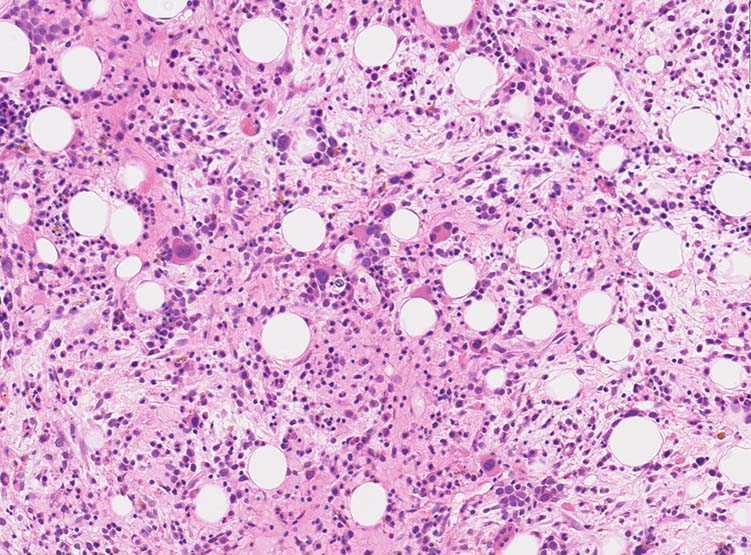

骨髄生検組織

1. 芽球増生の著明な髄様組織をしめすmegakaryoblastic leukaemia

2. 芽球の増殖が乏しく, myelofibrosisのみがめだつ2つのタイプがある。

骨髄生検組織: 骨梁は軽度に肥厚している. 明瞭な硬化像はない. 鍍銀染色でびまん性に線維増生が認められる.

AHEneu-OK.jpgBHEneu-hpf-OK.jpgCHE-oligo-hpf-OK.jpg

Bone marrow biopsy HE染色: A: 脂肪細胞は減少しているが線維化により造血細胞は疎になっている. B:小型Mgkが散在性に多数認められる.核は類円形, 小型低分葉の細胞が多く, 分離円形核をもつ異形成Mgkが出現している.

C:骨梁に沿って赤芽球が局在している. 通常は顆粒球系細胞が骨梁辺縁に局在する.

骨髄組織所見

正形成髄ないし過形成髄を呈する.

造血巣には, 巨核芽球と種々の成熟段階の異型巨核球が優位に増殖する. 両者の比率は症例によりさまざま.

小型巨核球が一様に増殖する症例では他のAML病型と形態的に区別ができないときがある.

巨核芽球とともに多数の成熟巨核球が増殖する症例もあるが, このときの成熟巨核球は一般に小型で, 低分葉核をもち異形成がめだつ.

微小巨核球が孤在性にあるいは集簇して多数認められる場合もある. クロマチンに濃染する1-2個の成熟核をもち成熟巨核球にみられる淡好酸性細胞質をわずかに有する細胞として見られる. 組織切片で巨核球系と同定するにはCD42b, CD61などの免疫染色が必要になる.

骨髄系, 赤芽球系の幼若細胞や異型細胞が混在することがあるが数はすくない.

骨髄線維症をともなうことがAML-M7の重要な特徴であるが, 必発ではない. 髄様の病変の症例がある.

弾性線維増殖であることが多いが, ところどころに膠原線維の増生を伴うことがある. (鍍銀染色, EVG, Azan染色で評価する)